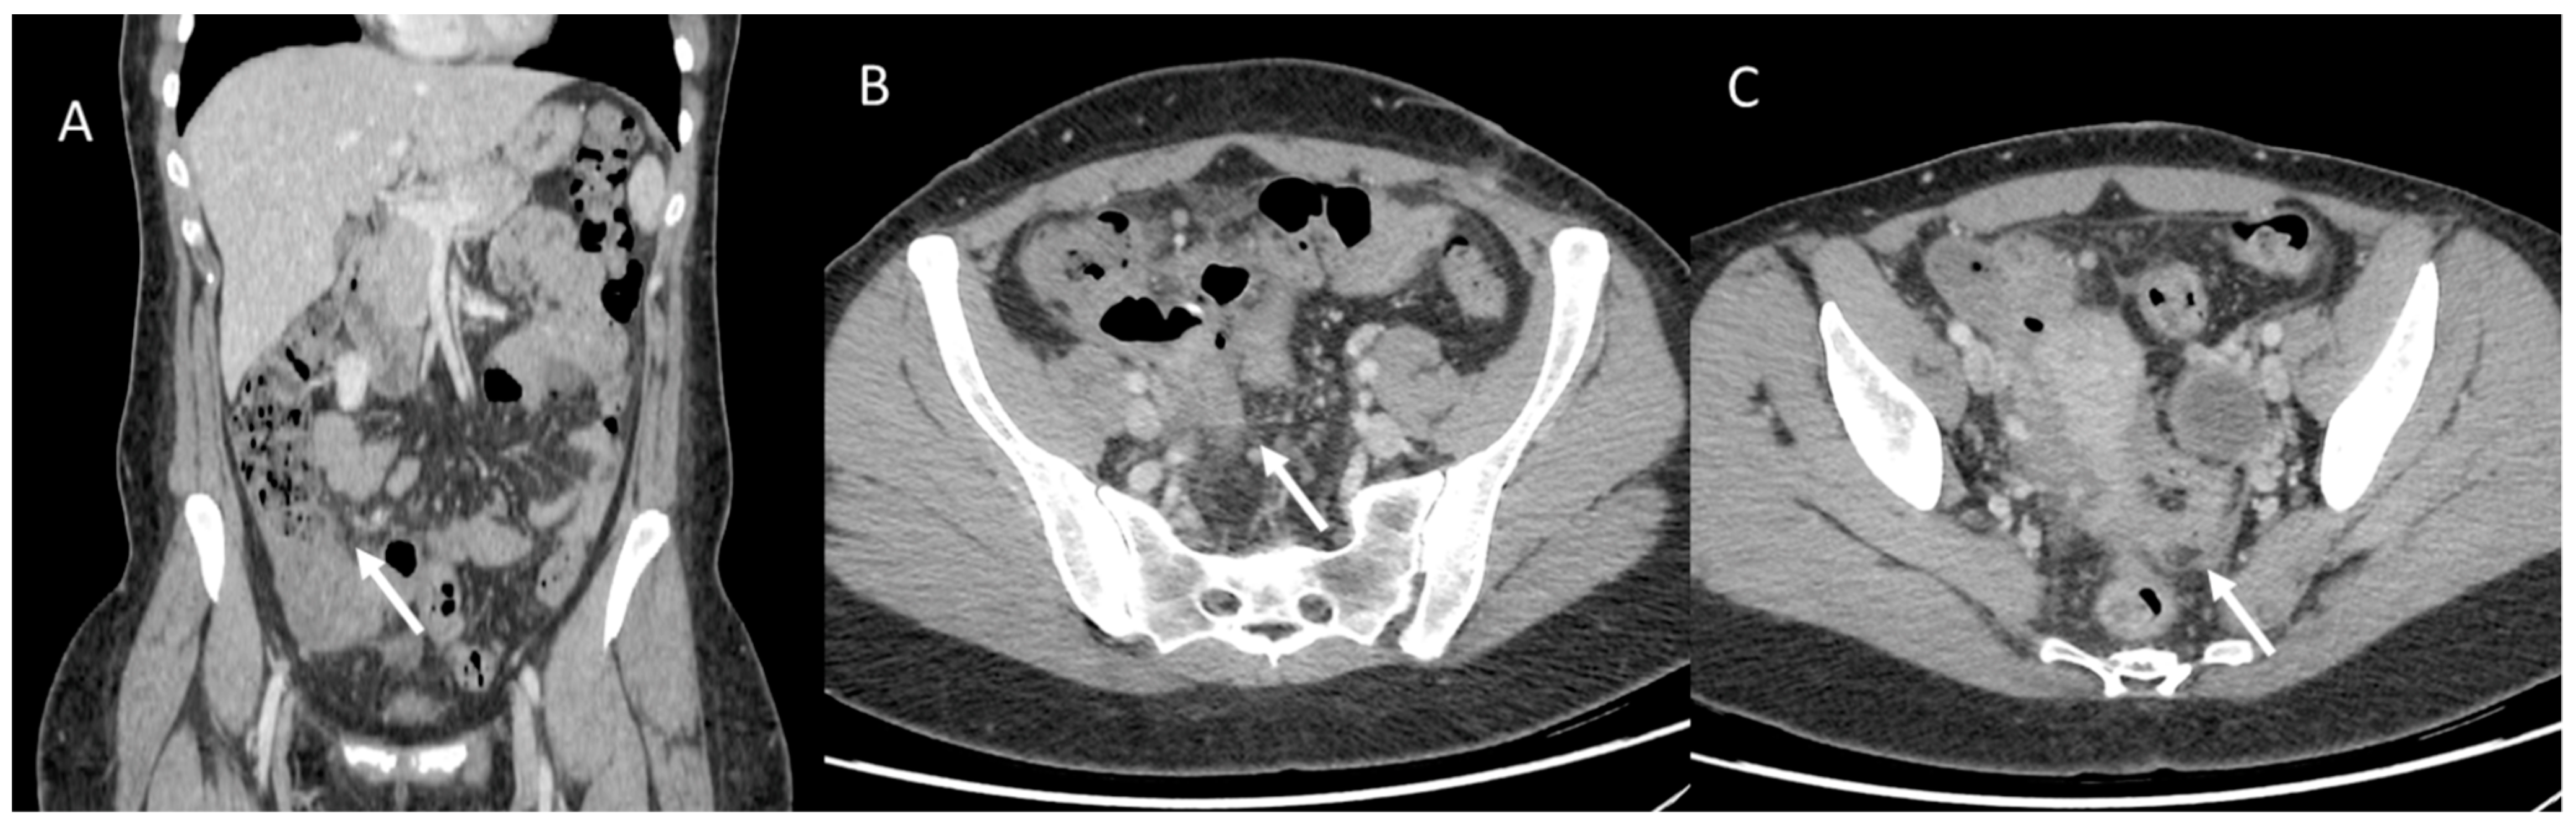

One study [103] investigated the survival of women with CF compared with men and showed that survival in the female population with CF is lower than that of men by about 5 years. Underlying this discrepancy is a different and higher anatomic-structural involvement on high-resolution chest CT (HRCT) in women with CF compared with men (Figure 3). Indeed, higher scores were recorded in women regarding the extent of bronchiectasis, involvement of bronchial branches, and severity of bronchiectasis, thus illustrating a virtually generalized involvement of the bronchial tree, as well as regarding air entrapment. This resulted in more frequent exacerbations, worse functional and nutritional outcomes, deterioration of quality of life, and greater structural damage in the female population.

Figure 3.

A woman and a man with CF with different and higher anatomo-structural involvement at HRCT in women with CF compared with men. (A) Diffuse cystic-varicoid bronchiectasis, with diffuse wall thickening and mucous plug (white arrow) in a young woman patient with cystic fibrosis. (B) Bronchiectasis with thickened walls (white arrow), especially in the medium-lower pulmonary lobes in a male patient with cystic fibrosis.